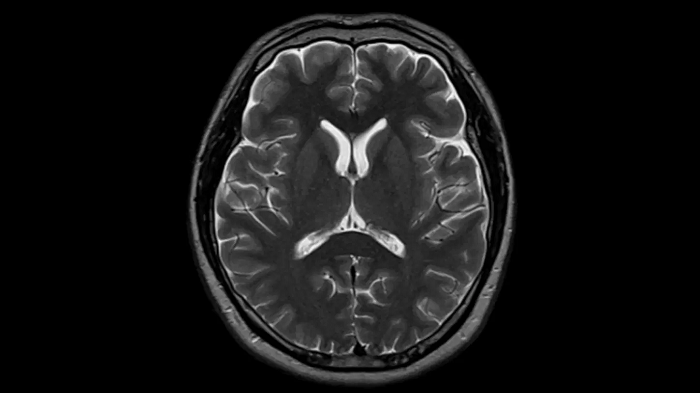

Head

T2 TSE with Deep Resolve

To produce high-resolution images, Deep Resolve, the Al-powered image reconstruction technology gets benefits from intelligent denoising and neural networks.

Deep Resolve Gain & Sharp

0.4 x 0.4 x 5.0 mm2

TA 2:50 min

MAC-ID: 7aaaa0195

MAC-ID: 7aaaa0195. Image Credit: Siemens Healthineers